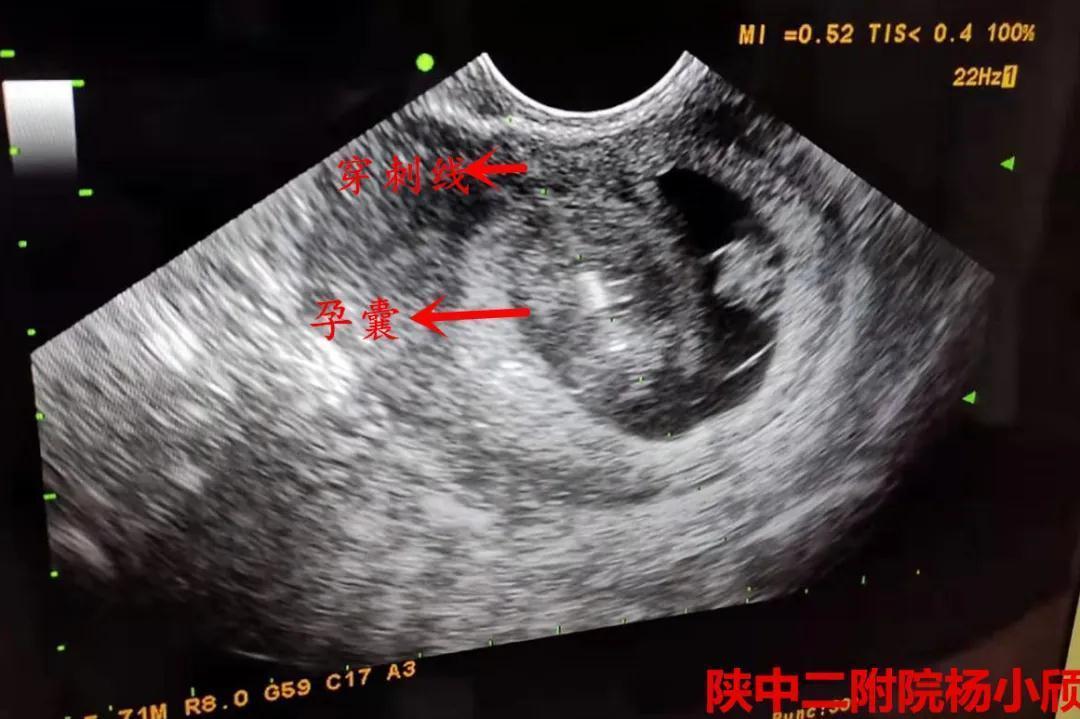

术中超声

在积极完善术前相关检查,排除手术禁忌症,充分告知患者及家属三胎妊娠的风险,签署知情同意书后,3月20日下午,杨小颀亲自操刀为患者实施了经阴道B超引导下选择性胚胎减灭术。手术顺利完成,病人病情平稳。术后24小时阴超提示,减胎孕囊胎心停止。7天后复查彩超提示,两胚胎存活,一胚胎停止发育。这标志着这台高难度的减胎手术圆满完成,达到预期效果,也再次彰显了陕西中医药大学第二附属医院(西咸新区中心医院)生殖内分泌科在减胎术方面的巨大进步。